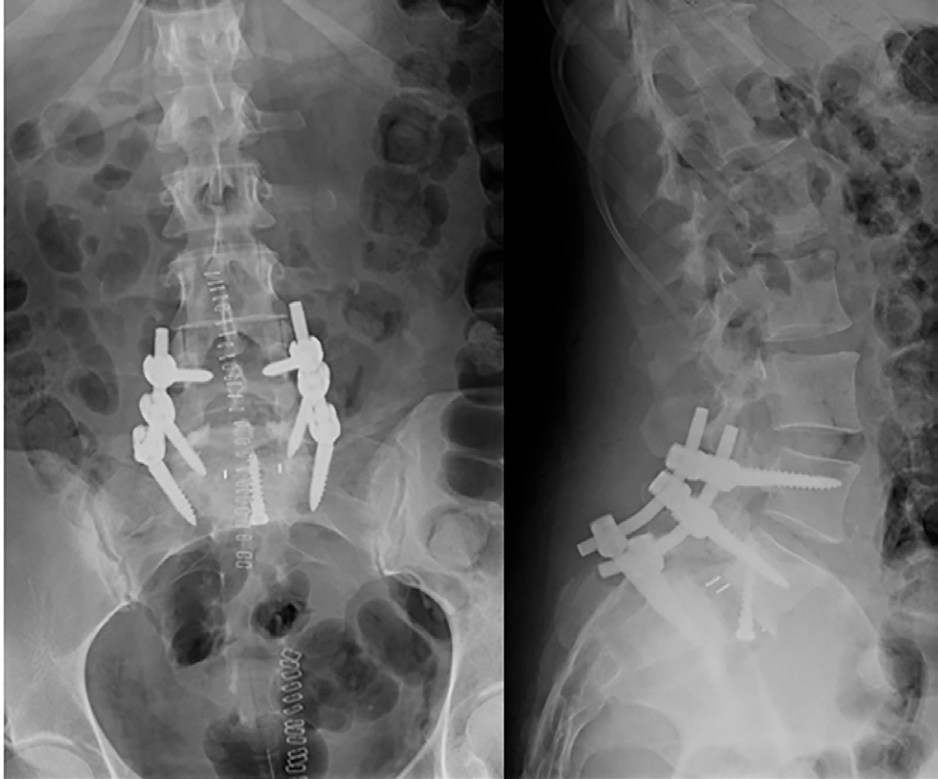

Bajo anestesia general, se realizó en un primer tiempo por vía anterior: discectomía y artrodesis ALIF mediante caja intersomática fijada solo a L5 para permitir el deslizamiento. En un segundo tiempo por vía posterior: fijación L4-S1 con tornillos pediculares y barras, previa reducción bajo control de escopia.

En el postoperatorio inmediato, la paciente es trasladada a UCI por anemización significativa y necesidad de soporte vasoactivo. Dada de alta de UCI al 3er día con buena evolución durante el resto del ingreso. No clínica radicular ni dolor lumbar y buena movilidad de MMII. Herida quirúrgica sin signos de infección. Alta a domicilio al 7º día postquirúrgico